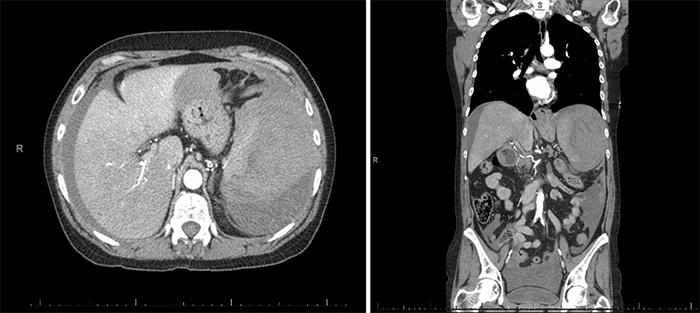

She was intermittently tachycardic and hypotensive but responsive to intravenous fluids. On abdominal exam, she was noted to be diffusely distended and tender, with peritoneal signs. Laboratory evaluation revealed a leukocytosis (WBC 21.4 K/uL), anemia (Hgb 8.6 g/dL), lactic acidosis (lactate 10.4 mmol/L), and AKI (Cr 2.2 mg/dL). She underwent a CTA of the chest, abdomen, and pelvis, which revealed a heterogeneous appearance of the spleen with associated hemoperitoneum (Figure 1).

Figure 1. Abdominal/Pelvic CT Scans. Published with Permission

Heterogeneous appearance of the spleen, with complex fluid in the left upper quadrant and free fluid in the abdomen and pelvis

Based on these findings concerning for splenic rupture, she was transferred to our facility for surgical care. En route, she became hypotensive, requiring blood product resuscitation, and stabilized transiently. On arrival at our facility, she was lethargic on exam and hypotensive and was taken emergently to the operating room.